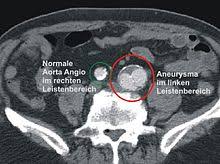

Ein Aneurysma im Gehirn muss zunächst keine Beschwerden hervorrufen. Die eines Eingriffs oder die dass die Aussackung platzt. Ein Aneurysma kann sich an jeder Arterie ausbilden häufig sind sie jedoch im Bauch in der Brust am Herzen oder im Gehirn.

Ein Aneurysma vor allem im Gehirn kann angeboren sein. Da das Schiff beginnt sich aufzublähen wird es wahrscheinlicher zu platzen. Niemand kann vorhersagen wann ein Aneurysma platzt und Leck Blut in die umliegenden Gebiete. Solange ein Aneurysma noch klein und intakt ist das Gefäß also keine Risse hat verursacht es häufig keinerlei oder nur unspezifische Beschwerden wie Kopfschmerzen oder Übelkeit. Wenn ein Blutgefäß erweitert oder Ballons durch Schwächung Wände heißt es ein Aneurysma. Je nach Größe und Lage des Aneurysmas im Gehirn können jedoch auch Beschwerden auftreten. Ein Aneurysma ist eine krankhafte Aussackung einer Schlagader. Fachleute gehen aber davon aus dass Aneurysmen mit einem Durchmesser unter sieben Millimetern nicht sofort behandelt werden müssen sondern beobachtet werden können. Je nach Größe und Ort sind weitere Symptome möglich.

Nicht rupturierte intrakranielle Aneurysmen finden sich bei etwa drei Prozent der Erwachsenen. Ein Aneurysma ist eine krankhafte Gefäßausstülpung also eine örtlich begrenzte Erweiterung einer Arterie. Ein Aneurysma ist eine krankhafte Gefäßausstülpung die sich an den hirnversorgenden Gefäßen zumeist an Gefäßaufzweigungen befindet. Die meisten Gefäßaussackungen im Kopf entdecken Ärzte durch Zufall oder weil sie Symptome wie beispielsweise Doppeltsehen verursachen. Täglich im Kühlschrank aufbewahren. Aber es lässt sich nicht ganz ausschließen dass auch solche kleinen Aneurysmen reißen. Niemand kann vorhersagen wann ein Aneurysma platzt und Leck Blut in die umliegenden Gebiete.